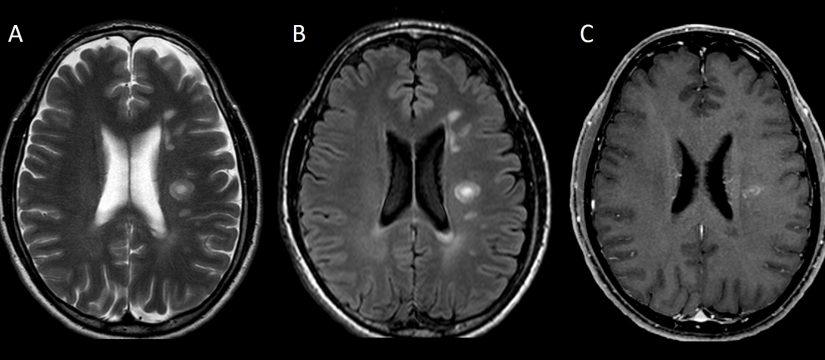

Historia Clínica

Varón de 40 años con esclerosis múltiple remitente-recurrente ya conocida, que consulta por disartria de varios días de evolución.